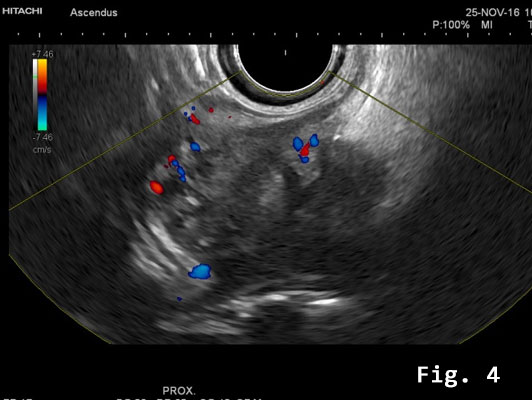

Endorectal endoscopic ultrasound of the sigmoid colon revealed transmural extension of the mass and confirmed the transcutaneous finding. The lesion was well vascularized [Figure 2].